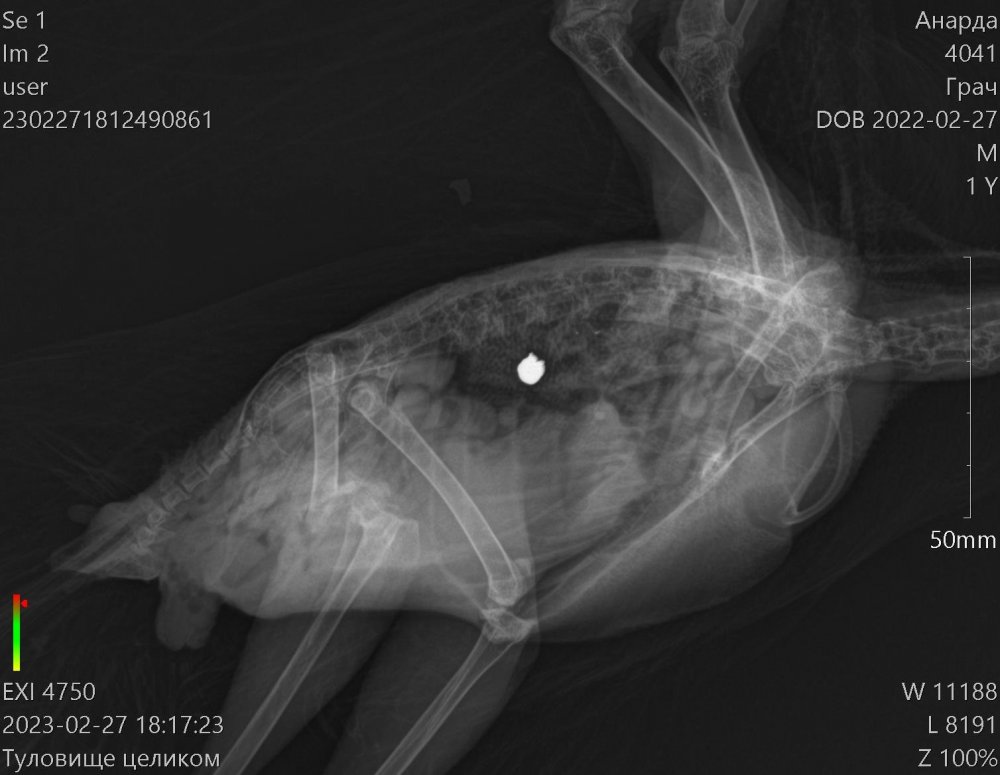

Доброго времени суток! Прошу строго меня не судить,так как оказался заложником ситуации ведь в отношении таких птиц не имел опыта совсем. Напишу вкратце. Шёл вечером домой,вижу лежит грач живой,ну я не смог пройти мимо и забрал его с собой.Повез к ветеринару,тот его пощупал и сказал что он травмирован и ничем помочь не может, сказал пусть поживёт у тебя месяц два, отойдёт и если все хорошо оклимется и улетит... Через месяц ничего не произошло, грач как хромал так и хромает, взлететь пытался но не смог. За это время я ему сделал вольер большой 2 метра в высоту и 5 в длину, научился правильно кормить. В общем понял что нарвался я на горе ветеринара и повёз в дорогую клинику, где сделали качественные снимки, оказалось его подстрелили, снимки прикреплю в тему. Сделали анализы, прописали лекарства, от паразитов, клещей итд. Но самое неприятное это то, что сказали что он летать не будет и ему нужна операция, каких у нас в Пятигорске нельзя осуществить. Подскажите пожалуйста, как нам быть? Кто сможет помочь нам? У нас в крае травили грызунов, средством которое запретили 35 лет назад, в итоге весь наш город и край усыпан трупами грачей, прямо везде даже в центре города,а своего я вроде думал что спас, но как оказалось нет :(